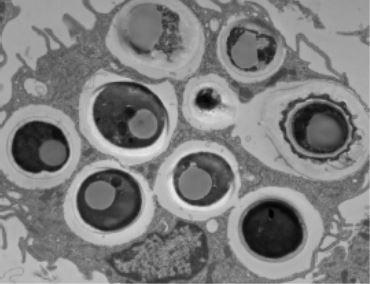

To identify the specific mechanisms at play, Dr. Stappenbeck and colleagues studied mouse models of impaired wound healing consistent with injuries observed in Crohn's patients, finding that D. hansenii levels were significantly higher only within unhealed wounds. They went on to find that the fungus preferentially localized within these wounds to a specific type of immune cell, called macrophages.